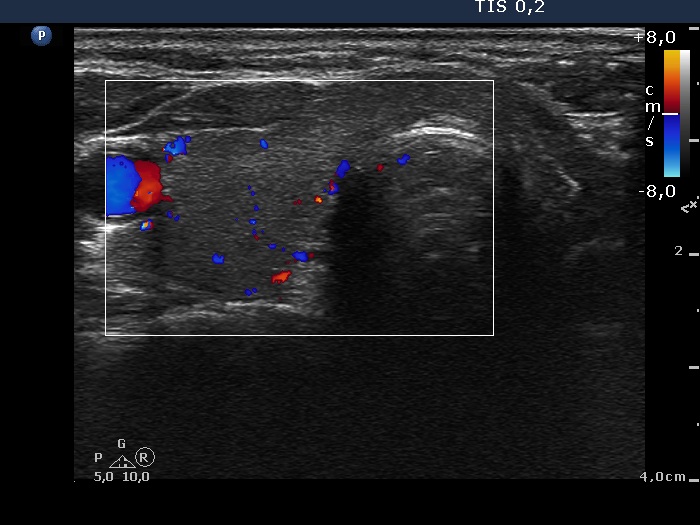

Ultrasonography. The right thyroid was moderately hypoechogenic without any circumscribed lesions. The left thyroid was removed. There were several enlarged lymph nodes in the right submandibular area. The largest one presented two discrete, more hypoechogenic intranodal lesions and a regular hilum.

Comment. This is an unusual case, the nodes (particularly those presented in the video) seem to be benign, reactive-type ones.